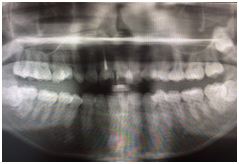

填寫完資料後,櫃台小姐告知我等一下會先帶我去拍一張全口數位X光,好讓醫生先了解我口內的大致狀況。

(拍完的2D影像,牙齒一覽無遺耶~太害羞了吧)